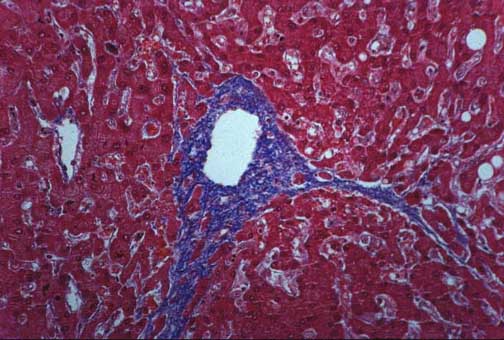

Fig. 10-2-3A. Cardiac fibrosis.

Marked dilatation and fibrosis of the central lobular vein with formation of fibrous bridges toward other lobules.